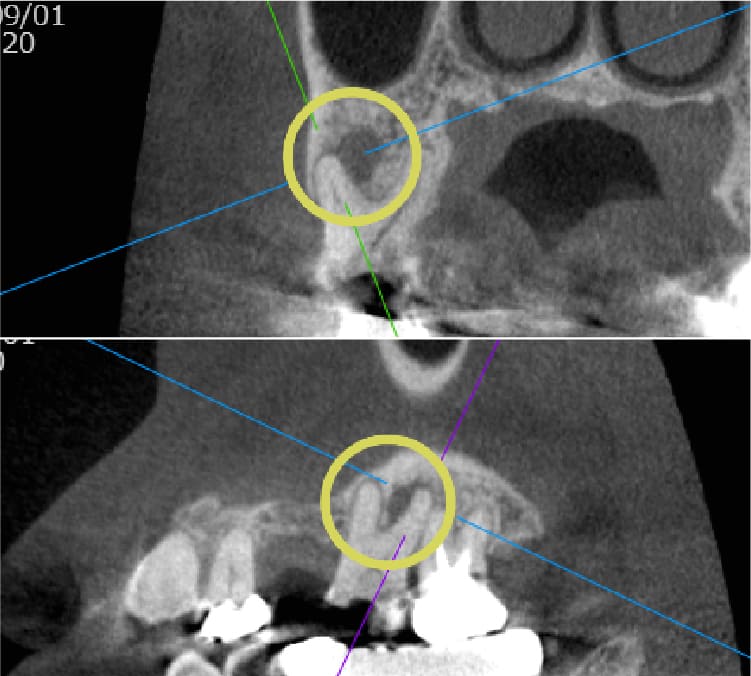

| 歯科用CTによる三次元診断 | 拡大ルーペの使用 |

| 一般的なレントゲン(二次元)では見えない、歯根の複雑な構造や病巣の位置を立体的に正確に把握し、治療の見落としを防ぎます。 | 肉眼では困難な根管内の細部を約8倍に拡大して確認し、処置の精度を高めます。 |

| 歯科用CTによる三次元診断 |

| 一般的なレントゲン(二次元)では見えない、歯根の複雑な構造や病巣の位置を立体的に正確に把握し、治療の見落としを防ぎます。 |